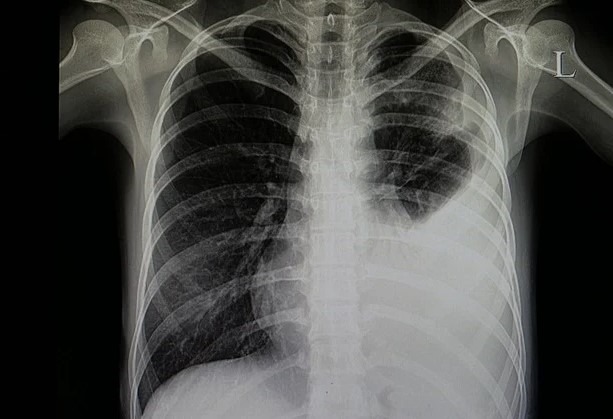

علائم بیماری پنومونی شامل تنفس سخت و سرفه با قاصدک، تب، درد در قفسه سینه، خستگی، تنگی نفس و افزایش ضربان قلب میباشد. برای تشخیص پنومونی، پزشک ممکن است از روشهای مختلفی مانند آزمایش خون، پرتونگاری سینه و یا جمع آوری نمونه از ریه استفاده کند.

اگر شما یا کسی در اطرافتان علائمی شبیه به پنومونی باکتریایی دارید، مهم است که به پزشک مراجعه کنید. پزشک با بررسی علائم، انجام آزمونهای تشخیصی مانند انجام ایکس ری سینه و آزمایش خون و تشخیص صحیح، درمان مناسب را برای شما تعیین خواهد کرد.

3. آزمون رادیولوژی سینه: ایکس-ری سینه و سی تی اسکن ممکن است برای تشخیص تغییرات در ساختار ریهها مانند التهاب، خونریزی، تجمع مایع و وجود التهابات باکتریایی استفاده شود.